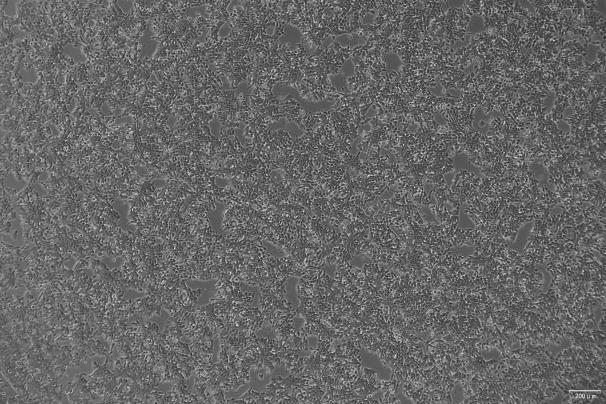

人视网膜神经胶质瘤细胞系(WERI-Rb-1)于1974年由R.M. McFall和T.W. Sery从一位患有视网膜母细胞瘤的1岁女性患者的人类视网膜神经胶质瘤细胞建立的。该细胞表现出葡萄状的圆形细胞簇,能在Difco Bacto-Agar中存活但不形成克隆。

悬浮生长;圆形细胞聚集成葡萄状 |